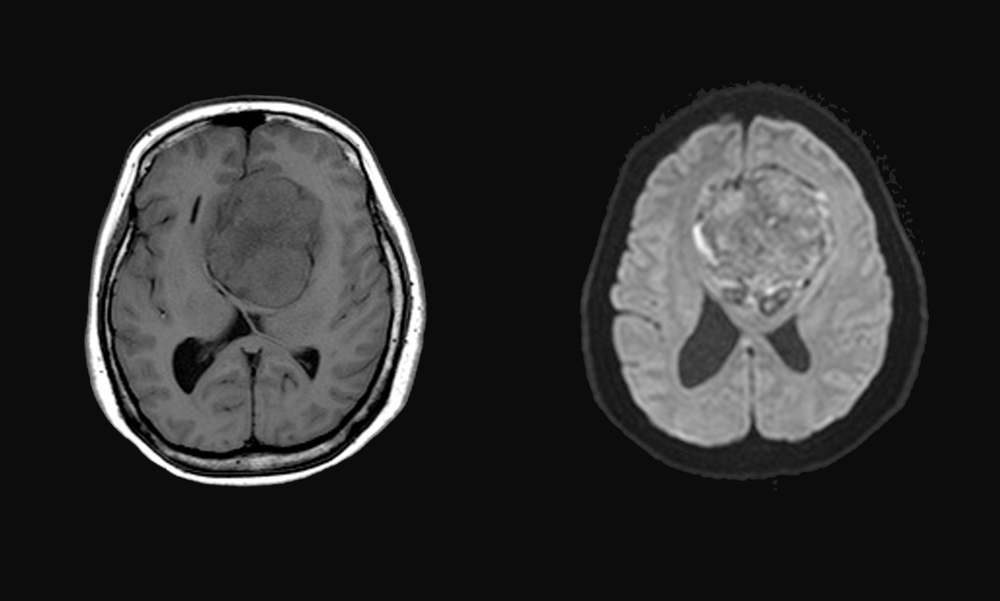

Depo-Provera Lawsuit Depo-Provera lawsuits are being investigated for women who developed meningioma brain tumors after receiving Depo-Provera birth control shots, claiming that Pfizer failed to adequately disclose side effects.